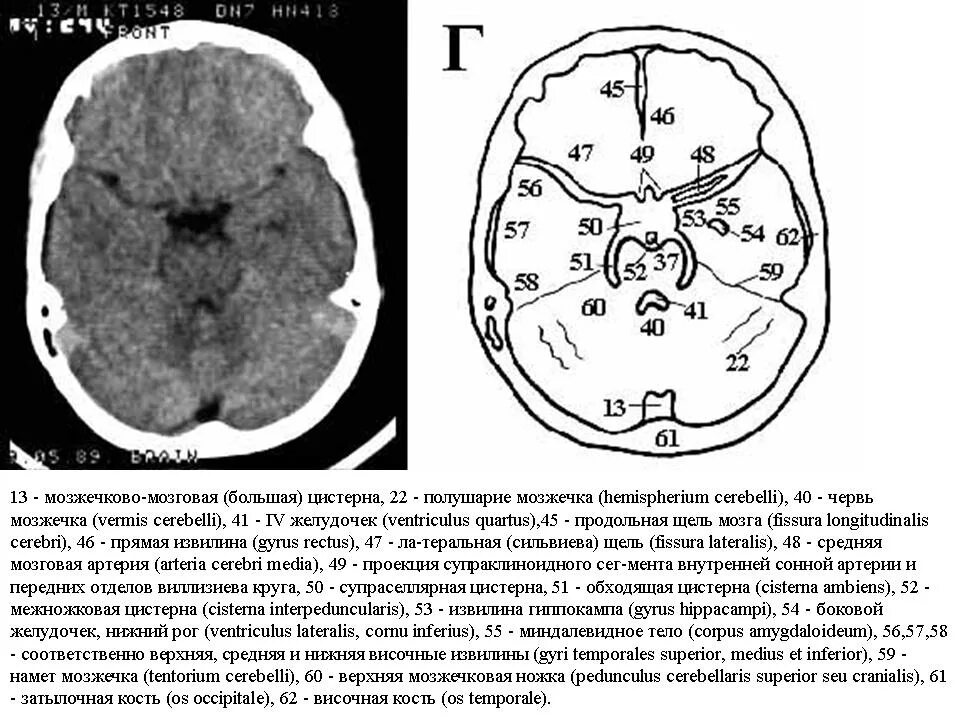

Цистерны на кт